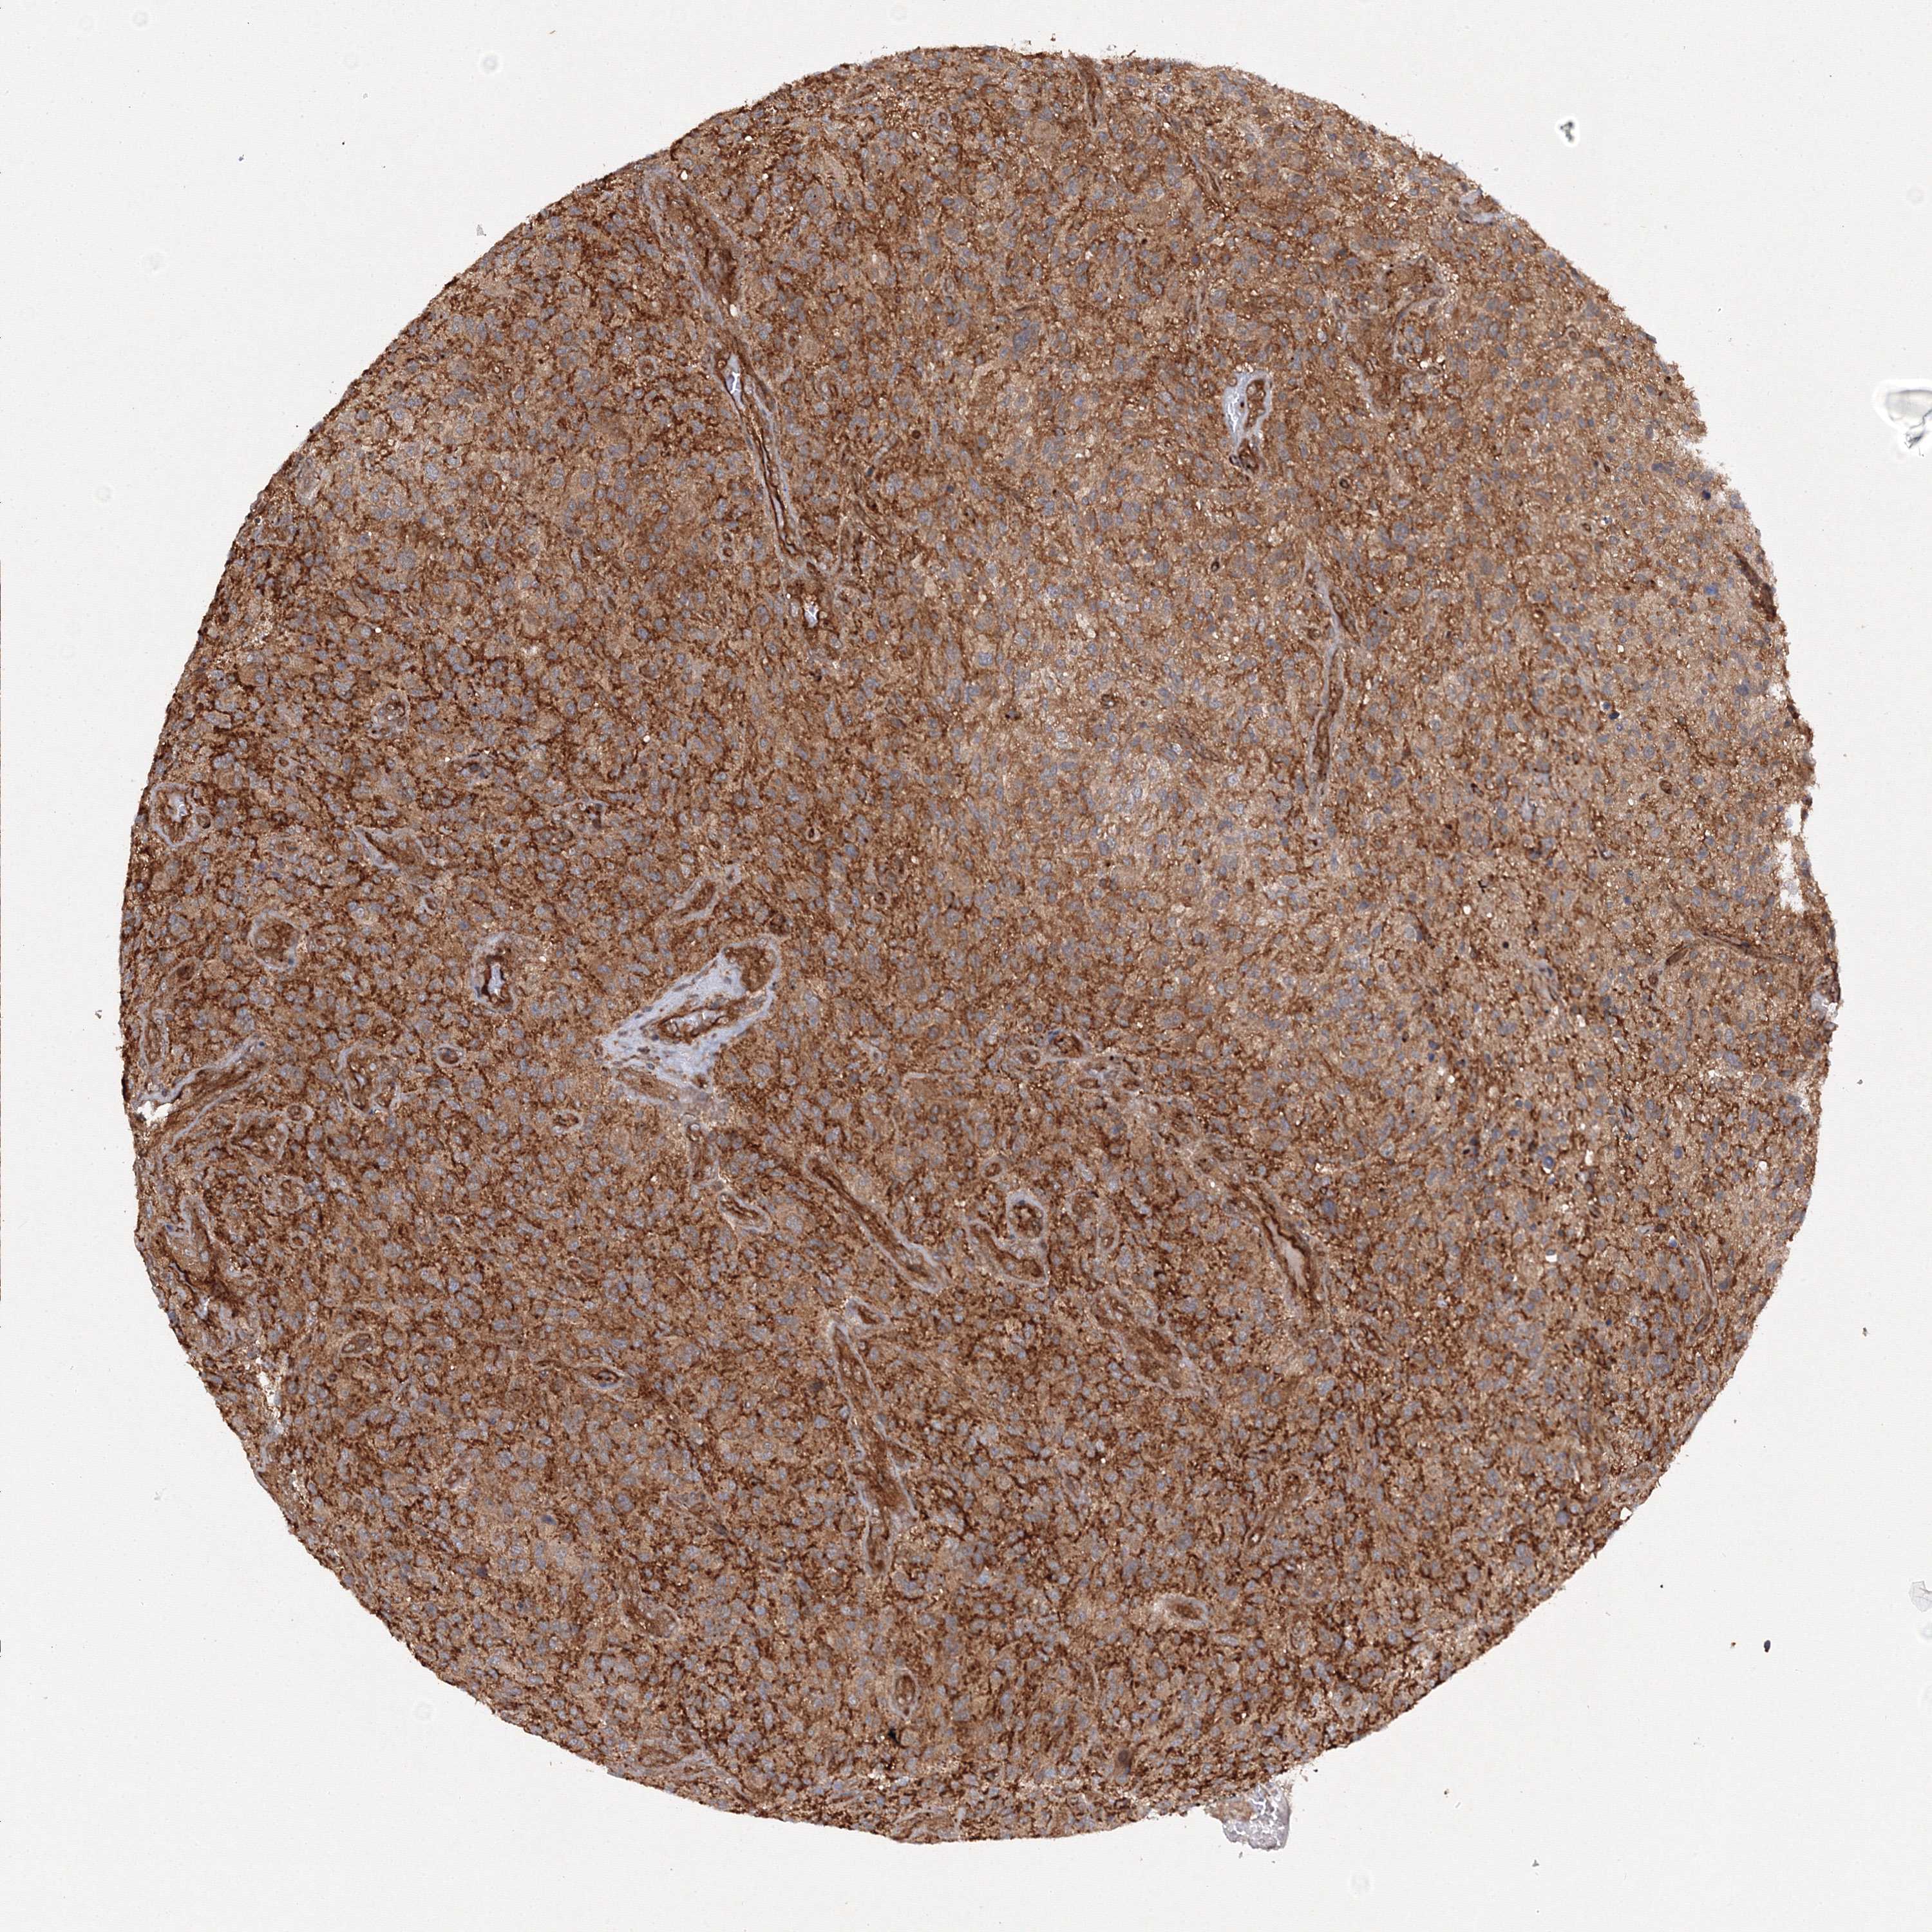

GLIOMA - Protein expressioni

A mouse-over function shows sample information and annotation data. Click on an image to view it in a full screen mode. Samples can be filtered based on level of antibody staining by selecting one or several of the following categories: high, medium, low and not detected. The assay and annotation is described here.

Note that samples used for immunohistochemistry by the Human Protein Atlas do not correspond to samples in the TCGA dataset.

Antibody stainingi

Antibody staining in the annotated cell types in the current human tissue is reported as not detected, low, medium, or high, based on conventional immunohistochemistry profiling in selected tissues. This score is based on the combination of the staining intensity and fraction of stained cells.

Each image is clickable and will lead to virtual microscopy that enables deeper exploration of all samples and also displays staining intensity scores, fraction scores and subcellular localization as well as patient and tissue information for each sample.

Antibody HPA035894

Staining

High

Medium

Low

Not detected

Intensity

Strong

Moderate

Weak

Negative

Quantity

>75%

75%-25%

<25%

None

Location

Nuclear

Cytoplasmic/membranous

Cytoplasmic/membranous,nuclear

Glioma, malignant, High grade

Glioma, malignant, Low grade

Glioblastoma, NOS